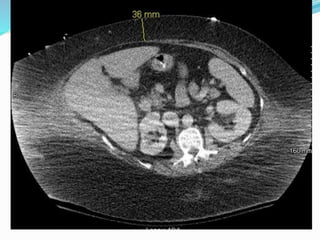

Parastomal hernia

 Incidence is unknown

due to underreporting

and difficult dx.

 Estimated to be between

20-80%

 More frequent with

colostomy than

ileostomy

 Cingi et al

 23 patients

 Patient examination

(PE) detected PSH in

52%

 CT detected total of

78%